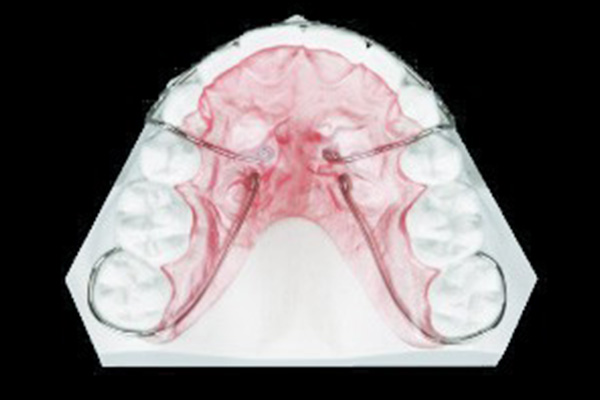

トランスパラタルアーチ

上顎につける装置です。一般的に左右の6番目の歯を繋げて固定する時に使われます。この装置とアンカースクリューを併用すると、歯全体を後ろに下げる事ができます。

使用例:抜歯症例、出っ歯等